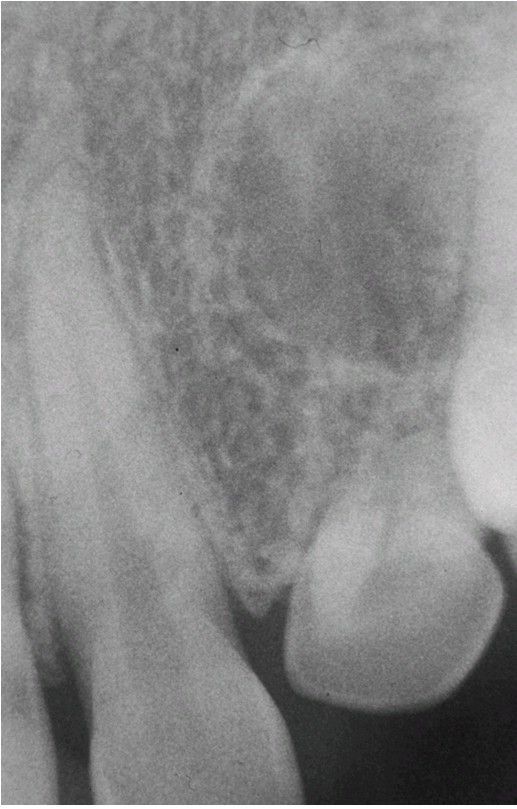

Tuberous Sclerosis radiograph

. Periapical radiograph exhibiting a well-defined radiolucency apical to the maxillary left lateral incisor. Biopsy revealed an intraosseous fibrous proliferation.